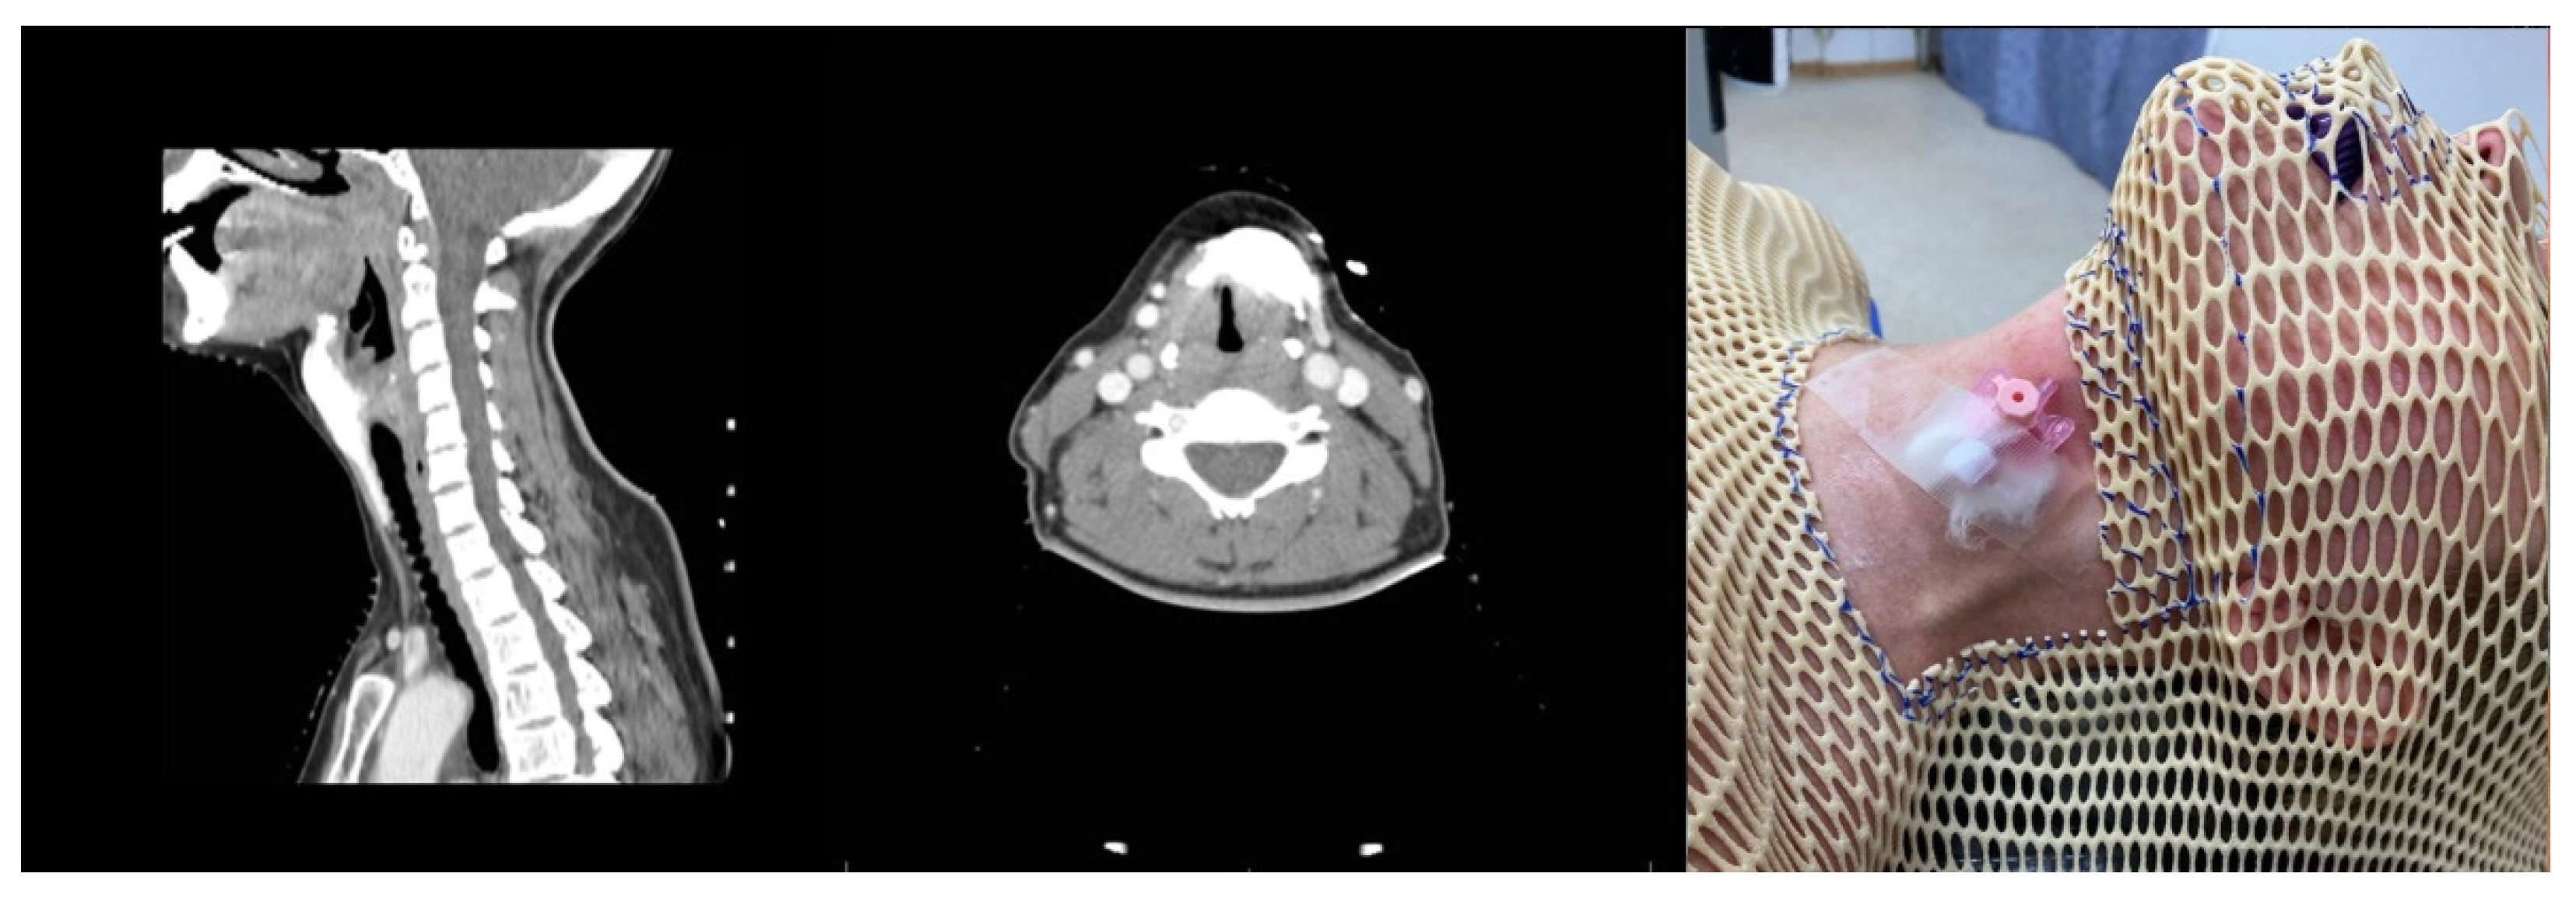

Patient M. was diagnosed with a median neck cyst. The patient underwent MSCT with intravenous contrast enhancement and cystography (Figure 2). The MSCT was performed in the patient’s selected position (the selected position is the uniform position of the patient during examination and surgery; in this example, it is the position in the CT scanner and on the operating table) on her back, in several stages. We used Q-fix (1 and 2) fixators produced in the USA in the form of a perforated thermoplastic cervicofacial mask-frame, with openings for operative access and intubation and designed for radiation therapy.

Cervical MSCT with intravenous contrast enhancement and cystography in the patient’s selected position, immobilized using a Q-fix system. Additional use of a bite splint installed between the central incisors to simulate the position of the lower jaw after intubation.

The examination revealed for the first time that the lump was 5 cm long and consisted of a cyst with a double-blind fistula descending from the cyst mass down to the lower edge of the isthmus of the thyroid gland (Figure 3).

The surgery was performed in the patient’s selected position—on her back, identical to the position during the MSCT (Figure 4).

Figure 4.

Referencing of the patient’s position in the operating room using a reference marker installed on a perforated thermoplastic cervicofacial mask-frame (left). Result: a 3D model of anatomical structures overlapping the patient as seen from the mixed reality glasses (right).

As a result, the fixation mask helped to ensure the patient’s position on the operating table, identical to that during the MSCT examination. However, the main disadvantage of this method lies in the need for the production of individual masks for each surgery and their installment during the preoperative process. This requires considerable time and labor costs.